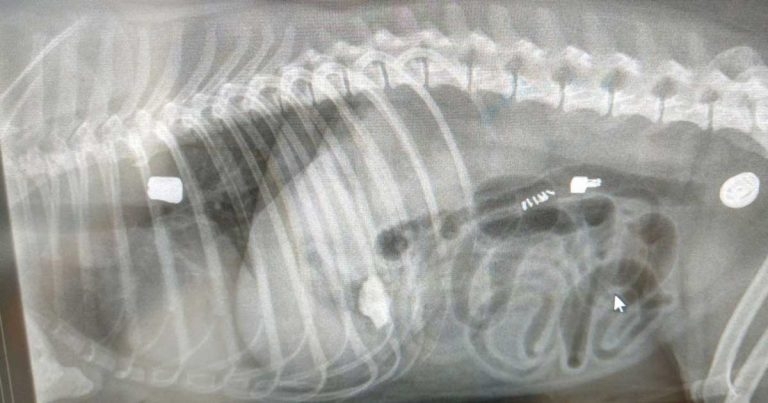

Figure 1. Initial lateral survey radiograph of thorax and abdomen, showing multiple radio-opaque foreign bodies.

An IV line was placed and the dog was sedated intravenously with medetomidine (20µg/kg) and buprenorphine (0.02mg/kg). On visual inspection, the throat and epiglottis were normal. Right lateral and dorsoventral thoracic and abdominal radiographs were then taken. A composition image is displayed (Figure 1).

The imaging identified oesophageal (dorsal and caudal to the heart base), gastric and intestinal foreign bodies, likely of metallic origin. The intestinal bodies were decided to be of lesser importance based on their further extent of passage. The clinical signs were most likely explained by the oesophageal and gastric foreign bodies. The owner was updated, and permission was given for general anaesthesia and endoscopy.